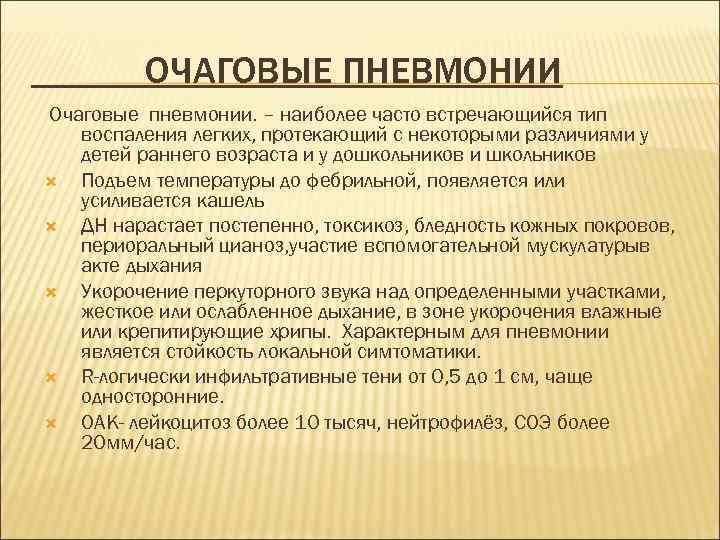

ОЧАГОВЫЕ ПНЕВМОНИИ Очаговые пневмонии. – наиболее часто встречающийся тип воспаления легких, протекающий с некоторыми различиями у детей раннего возраста и у дошкольников и школьников Подъем температуры до фебрильной, появляется или усиливается кашель ДН нарастает постепенно, токсикоз, бледность кожных покровов, периоральный цианоз, участие вспомогательной мускулатурыв акте дыхания Укорочение перкуторного звука над определенными участками, жесткое или ослабленное дыхание, в зоне укорочения влажные или крепитирующие хрипы. Характерным для пневмонии является стойкость локальной симтоматики. R-логически инфильтративные тени от 0, 5 до 1 см, чаще односторонние. ОАК- лейкоцитоз более 10 тысяч, нейтрофилёз, СОЭ более 20 мм/час.

Клиническая картина очаговой пневмонии у детей раннего возраста несколько иная . На первый план выступают признаки ДН, интоксикация, а физикальные изменения в легких чаще выявляются позже; процесс иногда носит двусторонний характер. В начальном периоде пневмонии у детей раннего возраста отмечаются катаральные изменения: насморк, сухой кашель, субфебрильная или фебрильная температура, нарушения общего состояния. Вялость, адинамия, мышечная гипотония, одышка ( отношение дыхания к пульсу от1: 2, 5 до 1: 1, 5 при норме 1: 3) с участием вспомогательных мышц в акте дыхания. При объективном осмотре обнаруживаются признаки вздутия легких; коробочный оттенок перкуторного звука, аускультативно-ослабленное дыхание.